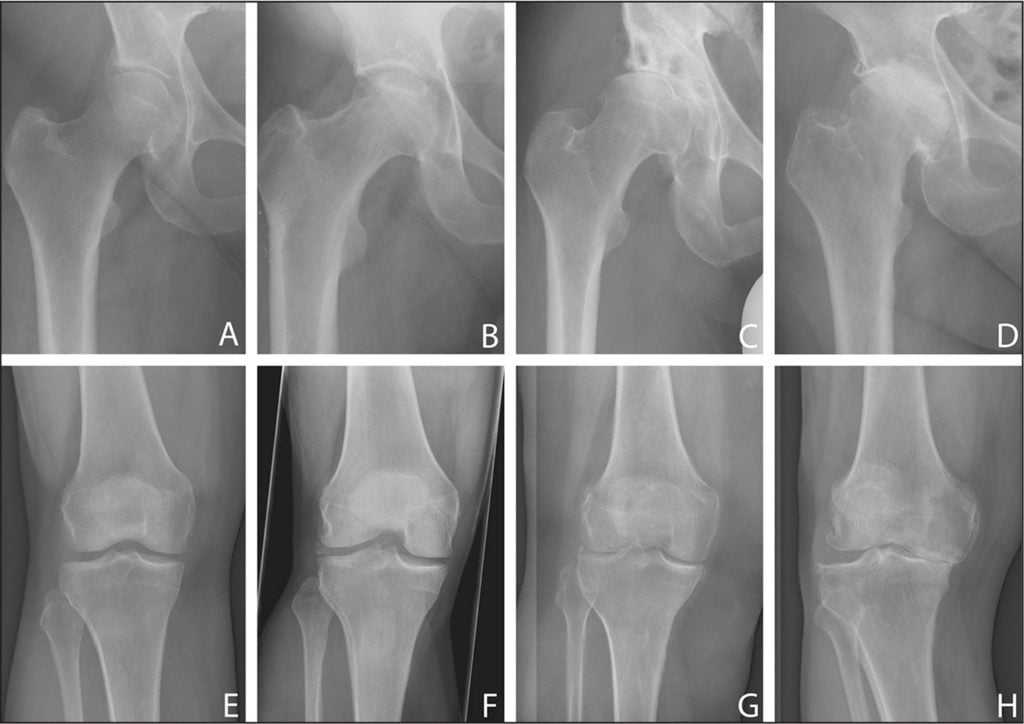

Степени остеоартроза тазобедренных суставов:

- 1 степени.

- 2 степени.

- 3 степени (лечение его будет более эффективным при хирургическом вмешательстве).

Слева направо — ухудшение состояния суставов по причине заболевания.

Остеоартроз тазобедренного сустава 1 степени, лечение которого будет эффективно медикаментозным путем, не провоцирует острых симптомов; мало кто из пациентов сразу обращается к врачу. Это влечет запускание болезни и переход ее в следующую степень протекания. На снимках рентгена еще не сильно заметны нарушения.

Остеоартроз тазобедренного сустава 2 степени характеризуется выраженным уменьшением пространства в суставной щели. В таком состоянии хрящи уже сильно повреждены, что провоцирует постоянное трение костей при движении и выраженную боль у пациента. Из-за развития отечности сустав теряет свои функции.

Выявить 2-ю степень несложно, так как при первом же рентгеновском снимке врач заметит существенные отклонения. Характерные признаки второй степени заболевания:

Заболевание поражает разные суставы. Коксартроз (артроз тазобедренных суставов) и гонартроз (артроз коленных суставов) – формы, которые зачастую приводят к инвалидности.